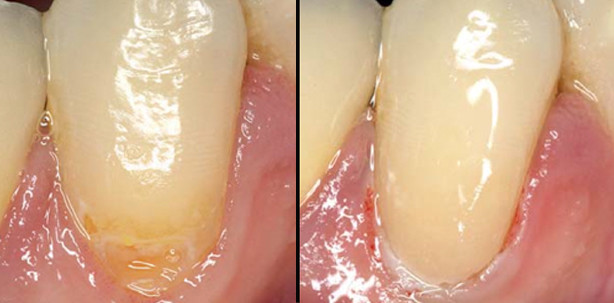

Abb. 4: Verschleifen und Polieren mit Sof-Lex Scheiben und Rädern. – Abb. 5: Situation nach erfolgter Therapie.

Die Überschüsse können mit einem Finierdiamanten entfernt und das Material mit Sof-Lex Scheiben geglättet werden. Zusätzlich wurden die neuen flexiblen Sof-Lex Polierrräder (3M ESPE) für die abschließende Oberflächenglättung verwendet. Gerade bei kariesaktiven Patienten wird durch die vorhandenen Fluoridionen eine Sekundärkaries verhindert. Mit zunehmendem Alter oder nach Schlaganfallleiden mit eingeschränkter Motorik sind diese Materialien ideal, um eine hydrolytische Degradation durch anhaftende Biofilme zu vermeiden.